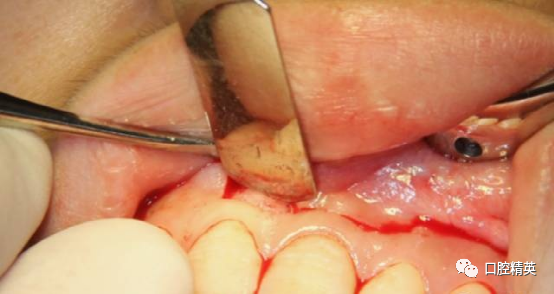

囊肿后壁与骨面粘连严重,术中破裂,可见大量豆渣样组织和药物颗粒。

初步清除。21根尖完全暴露。刮除21根尖区腭侧囊壁,此区域操作不便,易留有残留组织。